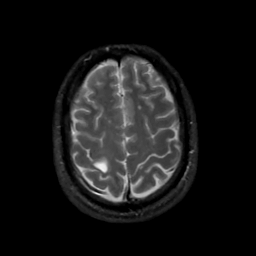

MR Study #10, April 28, 1991 -- Slice #40